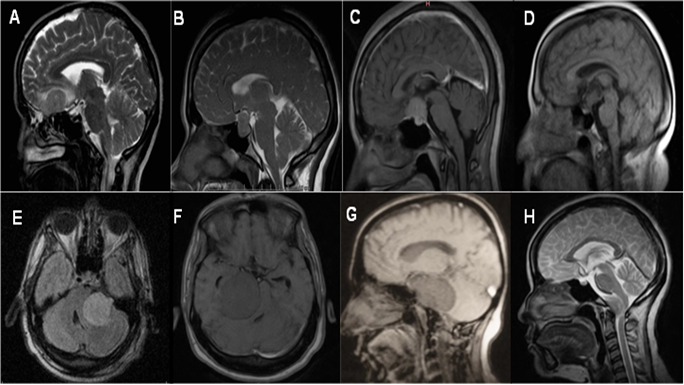

Figure 1: Imaging element that conforms the diagnostic triad are: A) Olfactory groove meningioma, extra-axial image on the cribriform plate of the ethmoid. B) Pituitary adenoma, image that deforms the sella turcica. C) Sellar tubercle menigioma, an image that rides on the sellar tubercle. D) Craniopharyngioma, suprasellar image of mixed intensity that respects the sella turcica. E) Petroclival meningioma, retroclival image that deforms the brain stem in the shape of an inverted comma. F) Cerebellopontine angle meningioma, an image in the cerebellopontine angle that deforms the brain stem in the shape of a comma. G) Chordoma of the clivus, image with destruction of the clivus. H) Cranio spinal junction meningioma, extra-axial anterolateral image, that displaces the medullary-medullary junction.

The in-depth clinical analysis of the endocrinological manifestations suggests greater involvement in craniopharyngiomas, while the bilateral ophthalmological alteration is in adenomas and craniopharyngiomas; however, unilateral visual disorder is more common in sellar tubercle meningioma due to its origin and tumor growth in the optic sulcus, except in tumors of considerable size that contact both optic sulcus in which bilateral visual alterations can be seen, but in a manner. Initially the affectation is unilateral. From the imaging perspective (Figure 1), adenomas frequently alter the morphology of the sellar region by increasing width, length, or destroying the sella turcica; Craniopharyngiomas continue their growth in the pituitary stalk with their variations in intensity, whether mixed by solid, cystic or combined component; and sellar tubercle meningioma due to their position on the sellar tubercle.

In the anterior cranial fossa, the olfactory Groove meningioma stands out and the diagnostic triad was accompanied by frontal headache, olfactory disorders and extra-axial image on the cribriform plate of the ethmoid. Clinical and imaging characteristics with a high association with these tumors (table 4). These lesions are characterized by growth in the sphenoidal plane, sellar tubercle, chiasmatic groove, sphenoidal limbus and sellar diaphragm [20]. Frontal headache is due to the inflammatory response in the meninges, compression of neurovascular structures or due to increased intracranial pressure; while alterations in olfaction due to irritation or deterioration of the olfactory fillets in the anterior fossa, and from the imaging perspective (Figure 1) are characterized by a space occupying lesion in this topography in contact with the arachnoid.

The diagnostic triad of the cerebellopontine angle meningioma are made up of: occipital headache, a seizure of the VII cranial nerve, and image of the cerebellopontine angle that deforms the brain stem in the shape of a comma. These lesions grow in the virtual space formed between the cerebellum and the brain stem [18,19], in relation to the internal auditory canal, which is why there is alteration of the VII cranial nerve and the lateral displacement in the form of a coma in an imaging study (Figure 1).

Regarding petroclival meningiomas, they stand out for the triad consisting of an occipital headache, seizure of the VI cranial nerve, and retroclival image that displaces the brain stem in the shape of an inverted comma. A differential element is diplopia due to involvement of the VI cranial nerve, given by alterations in its path in the stem towards the posterior wall of the clivus and through the Dorello canal within the basilar venous plexus [25]. While the displacement of the brain stem is anteroposterior, it adopts the shape of an inverted comma.

When analyzing the cranio-spinal junction meningioma, they presented the triad composed of: suboccipital headache, seizure of lower cranial nerves IX; these are due to tumor growth in the arachnoid surrounding the foramen magnum in the anterior or posterior segment and axial cervical portion, the topography where the real origin of the IX, X, and XI nerves lies at the level of the medulla oblongata [25].

Regarding chordomas of the clivus, they are accompanied by the diagnostic triad composed of: suboccipital headache; a seizure of the VI cranial nerve, and image that destroys the clivus. This type of lesion differs from petroclival meningiomas in the imaging characteristics, specifically in that chordomas have an origin in the remaining cells of the notochord, they can present a variable behavior with aggressive characteristics with alterations at the level of the clivus, including its destruction [24].